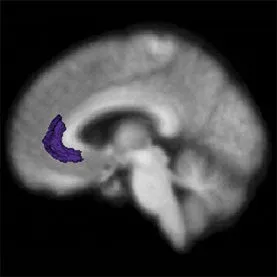

Het hoefijzervormige stukje op de foto is de . Dat is het hersendeel dat ons bewust maakt van ons gedrag in relatie tot anderen. Onderzoekers lieten proefpersonen taken verrichten waarvan je je opgelaten voelt. Bij mensen met gezonde

hersenen licht dat stukje op, bij mensen schaamte gebeurt daar niks. Die bevinding draagt ertoe bij om te vermoeden dat dat kleine witte vlekje de plek is waar onze persoonlijkheid zit. Of zoiets.